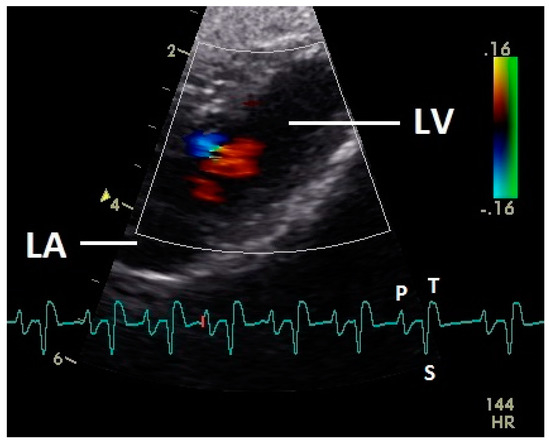

Figure 1.

Color Doppler image of the early diastolic filling of the left ventricle. The blood inflow in the left ventricle from the atrium (red signal) and vortex formation of the blood flow behind the septal part of the left atrioventricular (AV) valve leaflet and left outflow tract (blue signal) is visible. LV: left ventricle; HR heart rate. Electrocardiogram: P: P wave, S: S wave, T: T wave. The color scale on the right of the image is calibrated in m s−1.

Diastolic ventricular inflow was recorded in the atrium, across the AV valve and within the ventricular inlets and outlets. In the early diastole a red signal was recorded within the left atrium and across the mitral valve annulus into the left ventricle. This phase was interpreted as the passive ventricular filling due to left ventricular relaxation (descending part of T wave in ECG). Behind the longer septal part of the left AV valve leaflet and in the left outflow tract a blue signal in this phase of the cardiac cycle simultaneous to the red signal was observed in 42 birds (97.7%; Figure 1) and in the area of the lateral smaller parts of the left AV valve only in nine birds (20.9%; significant difference Chi-squared test p ≤ 0.001). In the mid diastolic phase in some pigeons the movement of the blood in the ventricle was observed (Figure 2). Within the P wave of the ECG an intense red blood flow signal was evident in the left atrium, crossing the left AV valve and entering the left ventricle as a sign of blood flow caused by atrial contraction. This rapid ventricular filling led to a visible blue signal in the left outflow tract, behind the septal part of the AV valve (97.7%), and in the some pigeons (48.8%; significant difference Chi-squared test p ≤ 0.001) also behind the smaller lateral leaflets of the left AV valve simultaneous to the red signal (Figure 3). In one pigeon the passive diastolic inflow was connected with the active ventricular filling (EA wave).